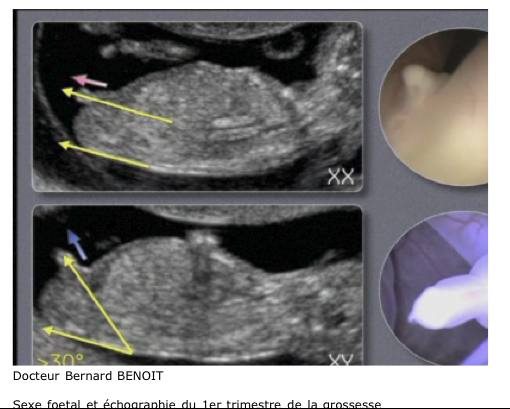

Determiner Le Sexe De Bebe Sur Votre Grossesse Au Jour Le Jour